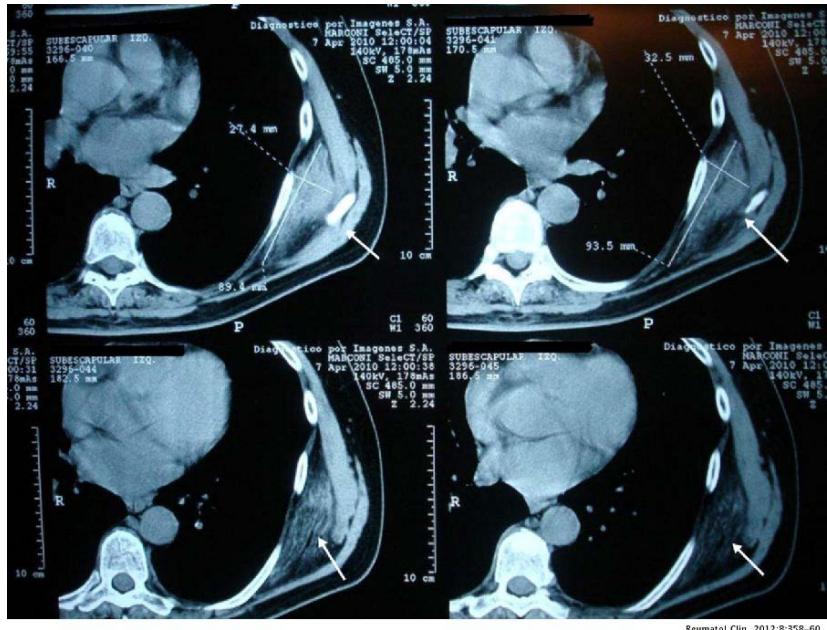

CT reveals an isodense structure with hypodense stripes \[21, 23\](Fig. 3).

Figure 3: An unenhanced CT scan shows a left subscapular mass that is in contact with intercostal muscles of similar density to skeletal muscle, with areas of weakness similar to subcutaneous fat (arrows).